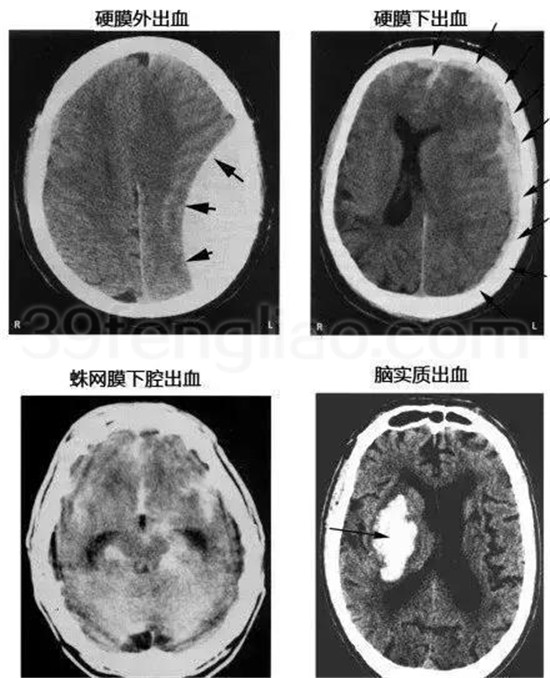

各种颅内出血

几种类型脑出血的CT表现